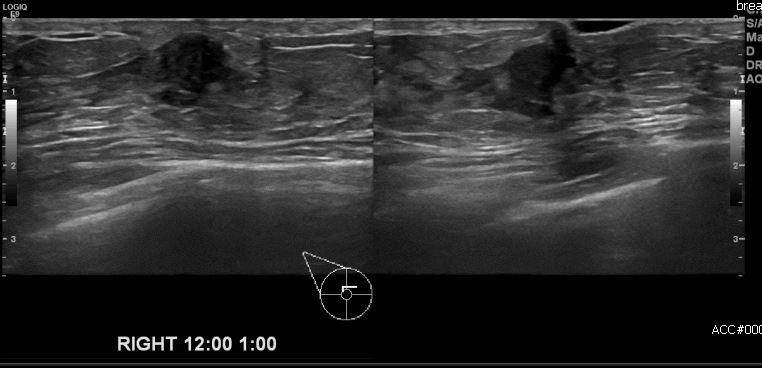

상기환자 우측 유방에 만져지는 멍울로 내원하시 30대 여성분으로 본원 초음파상    우측 12시에서 1시 방향에 으심스러운 멍울 조직검사 시행하여 우측 침윤성 유관암 진단

되었습니다.